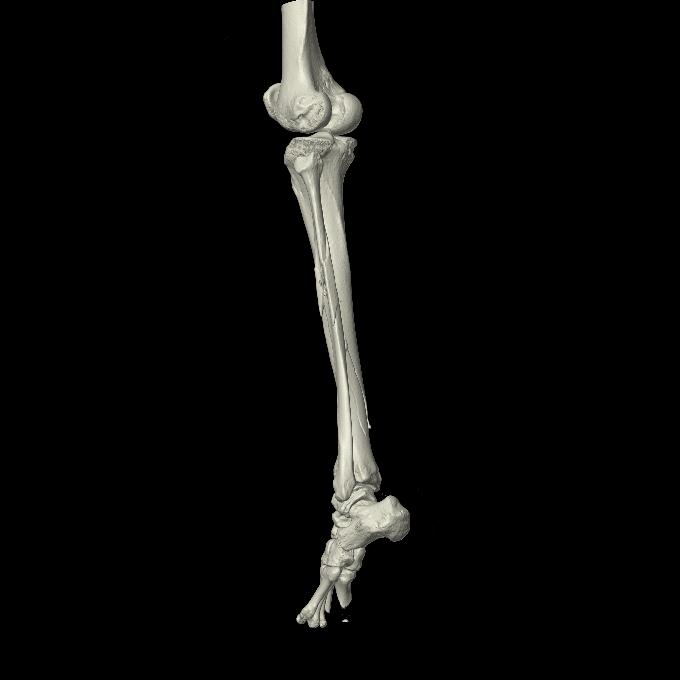

102803 1/12(キウスなし) 1/27 左下腿 4R 30歳女性 左脛骨軸内釘

102755 1/4 2R 1/15 2R 右足関節 68歳女性 右三果脱臼骨折